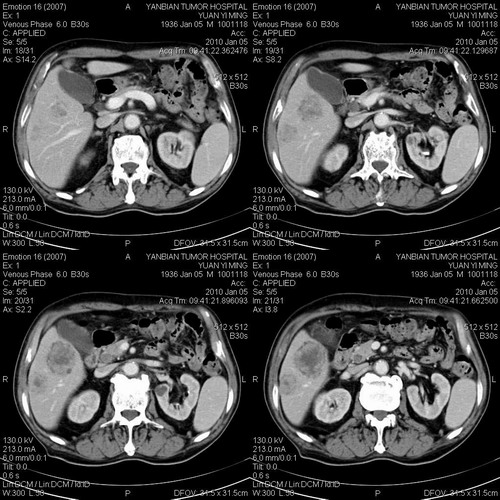

标题: CT24024:男,74岁。体检超声发现肝内多发占位性病变四天。 [打印本页]

标题: CT24024:男,74岁。体检超声发现肝内多发占位性病变四天。

并肝肾囊肿。

1)考虑肝脏恶性肿瘤(转移瘤?)。2)肝外胆管轻度扩张。3)左肾小囊肿。

考虑肝脏恶性肿瘤(转移瘤?)。2)肝外胆管轻度扩张。3)左肾小囊肿。